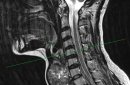

Фото: Пресс-центр Оренбургского государственного медицинского университета

Инновационный метод позволяет точно определить толщину и локализовать уровень расположения верхнего полюса щитовидной железы, осуществить его перевязку. Этот способ даёт возможности снизить риск развития таких осложнений, как кровотечение и повреждение верхнего гортанного нерва. Среди преимуществ новой методик — ее простота и возможность применения в любом стационаре, оборудованном томографом.